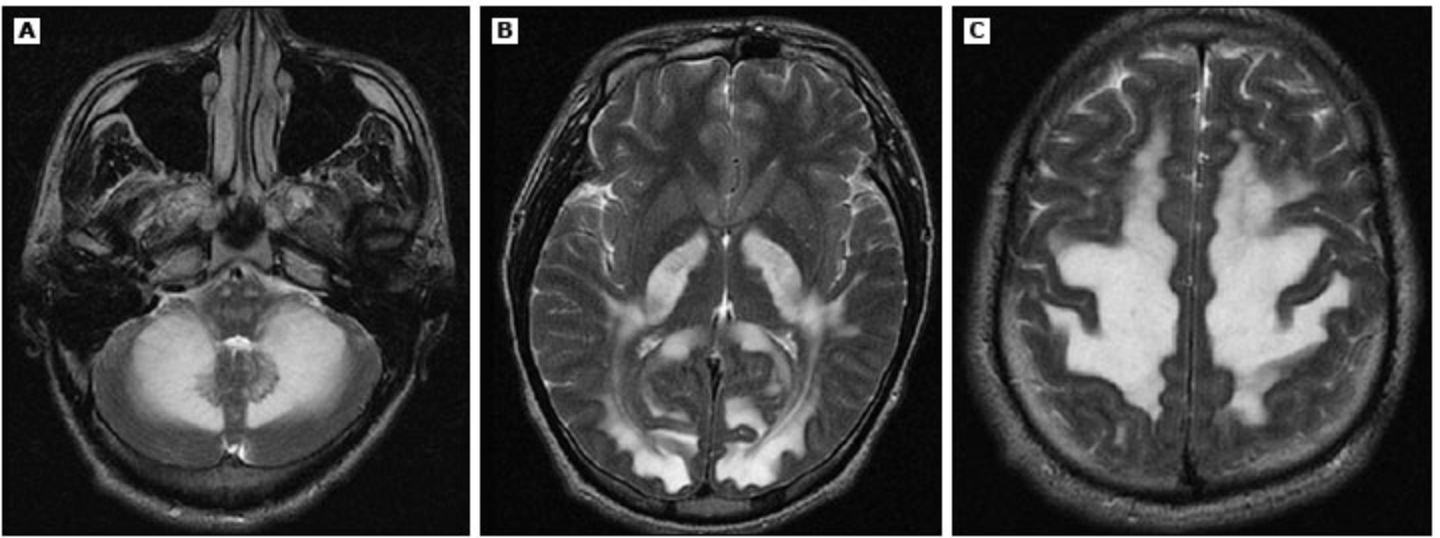

Following an organ transplantation, an immunosuppressed patient develops headaches, confusion, and cortical blindness. The following Head CT leads you to believe that the patient may be presenting with this syndrome.

What is posterior reversible encephalopathy syndrome (PRES) or reversible posterior leukoencephalopathy syndrome?